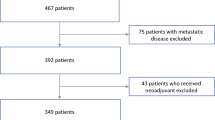

Both of the institutional review boards of the participating centers approved the retrospective study, and the requirement of the informed consent for patients was waived. According to the inclusion and exclusion criteria (Fig. 2), a total of 138 patients derived from two Chinese hospitals in different regions with pathologically confirmed PNET were recruited in our study. The patients from the two institutions were considered as training and validation cohorts respectively. The training cohort consisted of 104 patients (47 males and 57 females; mean age 52.4 ± 11.6 years; range 18–77 years) between April 2009 and November 2017 from Zhongshan Hospital of Fudan University, while the validation cohort contained 34 patients (15 males and 19 females; mean age 55.6 ± 12.5 years; range 19–82 years) between September 2009 and December 2017 from the Affiliated Hospital of Qingdao University. Clinical and radiological characteristics used in this study and the pathology analysis of the patients are described in Supplementary Information 1.

A total of 138 patients were contained in our study, among which 57 (41.3%) patients were categorized as grade 1, 69 (50%) patients were grade 2, and 12 (8.7%) patients were grade 3. No significant differences were found in age, gender, and histologic grade between the training and validation cohorts (Supplementary Table S1).